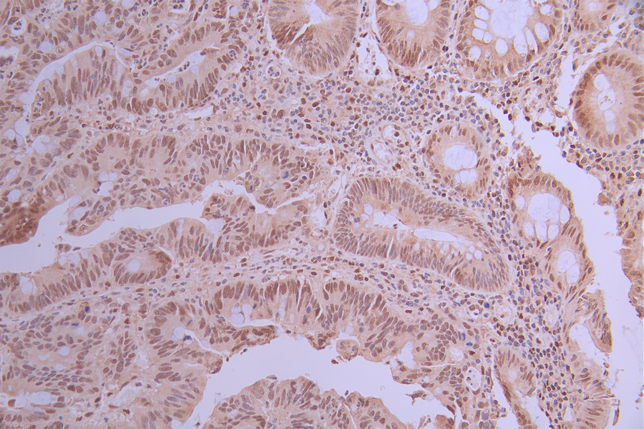

IHC image of CSB-RA935455A0HU diluted at 1:100 and staining in paraffin-embedded human colorectal cancer performed on a Leica BondTM system. After dewaxing and hydration, antigen retrieval was mediated by high pressure in a citrate buffer (pH 6.0). Section was blocked with 10% normal goat serum 30min at RT. Then primary antibody (1% BSA) was incubated at 4°C overnight. The primary is detected by a Goat anti-rabbit polymer IgG labeled by HRP and visualized using 0.05% DAB.